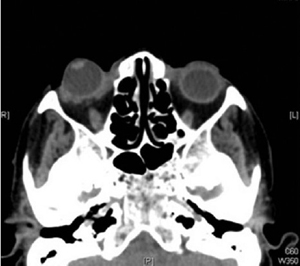

一名 65 岁女性因右眼剧烈疼痛就诊于我院急诊,自述 3 小时前有右眼门把手外伤史。查体发现右眼视力为手动,上下眼睑均位于脱位的眼球后,眼压为 54mmHg,角膜水肿,前房较深,视网膜窥不甚清(图 1)。左眼检查无明显异常。急诊首诊医生诊断为球后出血,急予以头颅及眼眶 CT 扫描,CT 则仅发现眼球脱位、眼睑肿胀,并无颅内、眶内出血抑或眶壁骨折的征象(图 2),B 超检查并未发现视神经撕脱的证据。

图 2 眼眶 CT 无眶内出血及眼眶骨折